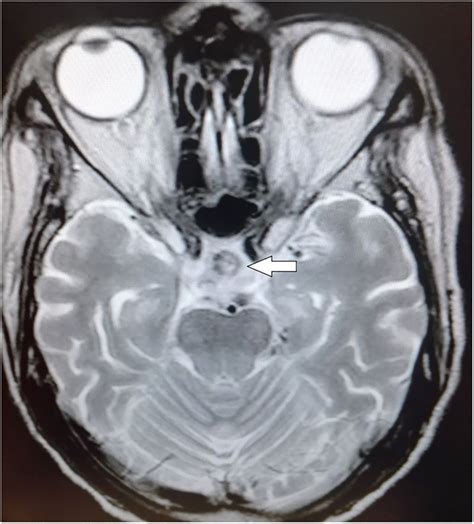

• Vascular Issues: Vascular issues, such as aneurysms or vascular malformations, can be detected on an MRI scan. These conditions can affect blood flow to the pituitary gland and cause symptoms.

• CT Scan: A computed tomography (CT) scan uses X-rays to produce detailed images of the body. While CT scans can provide useful information about the pituitary gland, they are generally less effective than MRI scans for detecting soft tissue abnormalities.